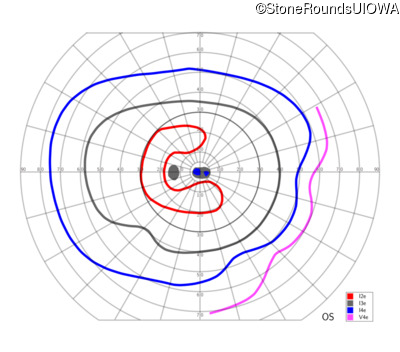

This 52 year old man had normal vision until his mid 30's when he began to have trouble distinguishing colors. the issuing 10 years he had a gradual loss of visual acuity accompanied by increasing photophobia.

| Age at visit: 58 years |